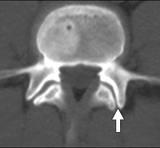

Tropismi puhul siis fassettliigestes assümmeetria. Umbes nagu siin.